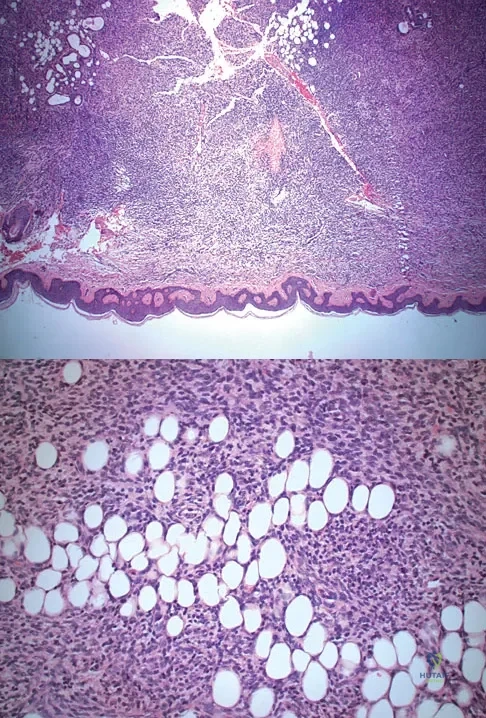

Question 29

A 43-year-old woman is referred after excisional biopsy of a cutaneous soft-tissue mass from her left shoulder. Based on the biopsy specimens shown in Figures 44a and 44b, what is the best course of action?

Explanation